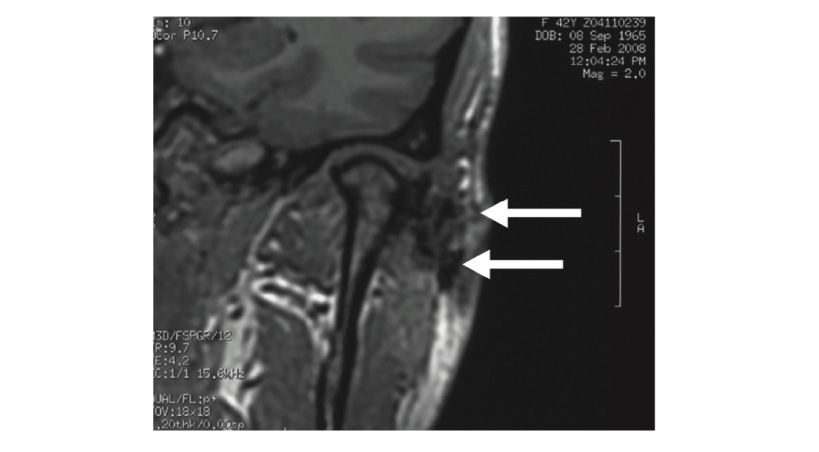

Artrocentesis para trastornos de la articulación temporomandibular

Un metanálisis en red de ensayos controlados aleatorizados.